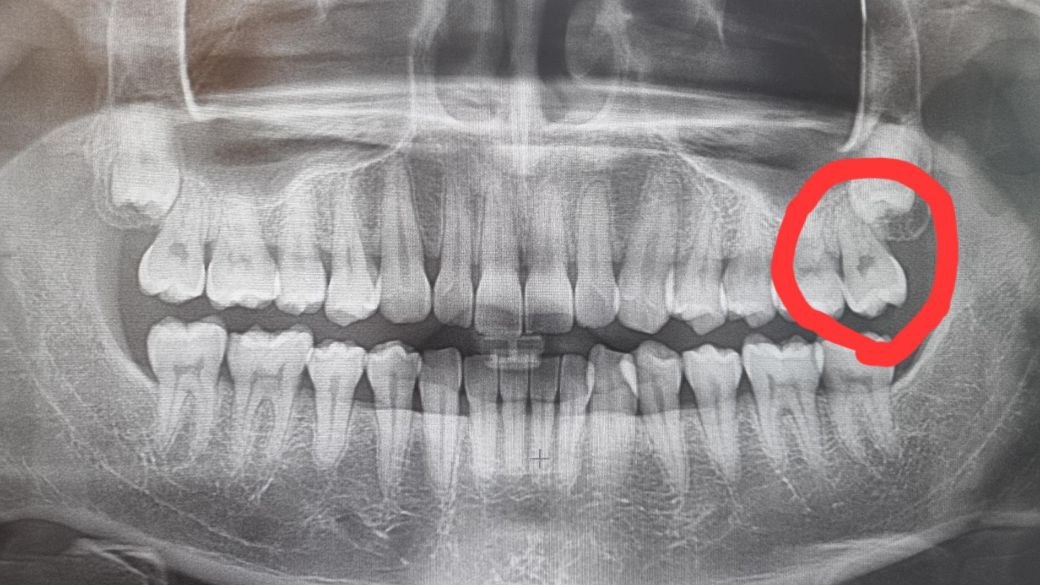

충치가 원래 X-ray 상으로는 잘 안보이나요? (x-ray, 치아 사진 첨부)

충치 치아는 왼쪽 위 맨끝 어금니 입니다.

그런데 제가 충치가 얼마나 깊은지는 알 수 없냐? x-ray에 보이지는 않냐? 라고 여쭸는데 x-ray에서는 잘 안보이고 충치치료하며 파봐야 얼마나 깊은지 알 수 있다고 하더라고요.

그게 좀 의아해서요...보통 x-ray로 얼마나 깊은지 확인하는걸로 아는데...

선생님들이 보기에는 충치가 있어 보이실까요?

그리고 x-ray상으로 충치가 안보이는게 흔한일 인가요?

• 2번 째 사진

1. 외견상 씹는면에 충치가 있어보이는 건 맞고, 엑스레이상 나타날 정도의 깊은 충치는 아닌 것으로 보이나 실제로 충치 제거하면서 파고 들어가다보면 예상외로 깊은 경우도 간혹 있습니다.

2. 엑스레이 사진은 왜곡, 축소가 일어나는 경우가 많습니다. 찍는 각도에 따라서도 다 다다르게 보이고요.